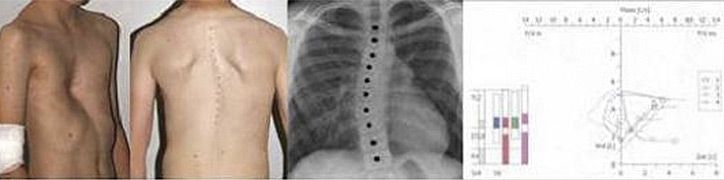

- Falsche Körperhaltung, Entwicklung einer Wirbelsäulenverkrümmung (Skoliose)

- Vermessung und Fotodokumentation des Befundes

- Röntgenbild des Brustkorbes in 2 Ebenen